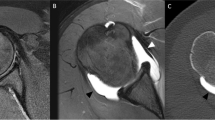

a–c CR true A-P view or Grashey view images, c magnified view of b with anatomy defined. In a, the radiolucent glenohumeral space indicates the regular anatomical relationships. In b–c, the intersection of the profiles of the scapular glenoid and humeral head is a radiographic sign of posterior dislocation of the shoulder (“crossover sign”)

As the scapula is located at the superior posterolateral part of the chest, the actual AP radiograph of the glenohumeral joint is obtained by administering X-rays with an angle of 45° from the medial aspect towards the lateral direction. These plain films may be obtained in the supine or standing position. The major advantages of the actual AP- Grashey projection over conventional AP radiographs are outlining the glenohumeral joint and characterizing the glenoid clearly from the humeral head (Fig. 11). If the humeral head overlaps the scapular glenoid on this projection, it means that the glenohumeral joint is dislocated either anteriorly or posteriorly. Grashey view is the most valuable for the diagnosis of fractures of the coracoid, glenoid, and proximal humerus but mainly for posterior glenohumeral instability.